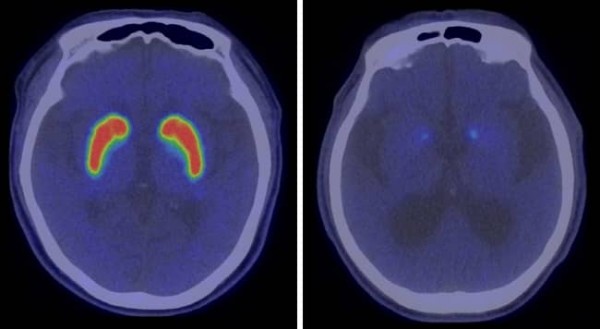

이 환자는 요추 사이 공간을 통한 뇌척수액 배액술 후 보행장애가 크게 개선되어 정상압 수두증으로 진단됐다. 그런데 렘수면행동장애(수면 상태에서 비정상적으로 근육의 긴장이 낮아지지 않아 꿈의 내용을 실제 행동으로 옮기는 증상)와 서동증(행동 느림)이 두드러지게 나타났고, 도파민 운반체 양전자방출단층촬영(PET) 검사에서도 파킨슨병이 의심되는 결과가 확인됐다.

신경과 박영호 교수는 “정상압 수두증은 70세 이상 노인 100명 중 두 명에서 볼 수 있는 비교적 흔한 질환”이라며, “이 환자의 경우 정상압 수두증으로 진단받았지만 렘수면행동장애와 서동증이 심해 실시한 PET 검사에서 파킨슨병 소견이 나타나, 뇌척수액 배액과 함께 파킨슨병 약제를 복용하며 증상이 더욱 개선된 경우”라고 말했다.

사진 2. 정상 뇌(좌)와 파킨슨병 환자의 뇌(우) 도파민 운반체 PET 비교 영상

정상 뇌에 비해 오른쪽 파킨슨병 환자의 뇌에서는 기저핵 부위에 반응이 약하게 나타나는 것을 확인할 수 있다.